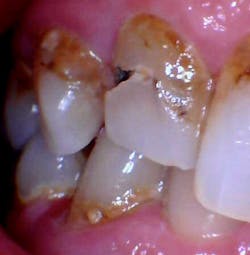

His situation was more involved than anticipated (figures 1–3), which, to address properly, would more or less require a full mouth of crowns, scaling and root planing, and a 360-degree turnaround of his oral health home-care management.

2. The patient has HUGE apple core cavities, large existing fillings with caries, and they all need crowns to restore. I’m more or less at a point in my career when I just don’t do BAFs (big-ass fillings) anymore, and if I do, it’s on a very rare occasion. Why? Because there are limitations to our restorative materials (and my patience!), and if I’m spending 30 minutes trying to get a seal on a resin that wraps around a tooth in 10 different directions, it’s not worth my time and headache. I don’t like putting myself or my patients in a situation where they have to come back again and again for the same thing. They are spending their money two to three times over for restorative work, even if it’s for something to “get them by.” Tough love? Perhaps, but I’m calling the shots here, not the patient.